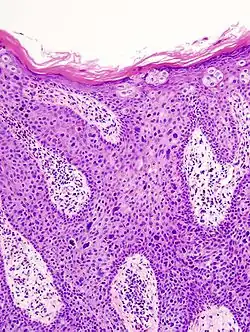

Histological characteristics

Histopathologically, the epidermis in cSCC in situ (Bowen's disease) will show hyperkeratosis and parakeratosis. There will also be marked acanthosis with elongation and thickening of the rete ridges. These changes will overly keratinocytic cells, which are often highly atypical and may have a more unusual appearance than invasive cSCC. The atypia spans the full thickness of the epidermis, with the keratinocytes demonstrating intense mitotic activity, pleomorphism, and greatly enlarged nuclei. They will also show a loss of maturity and polarity, giving the epidermis a disordered or "windblown" appearance.

Two types of multinucleated cells may be seen: the first will present as a multinucleated giant cell, and the second will appear as a dyskeratotic cell engulfed in the cytoplasm of a keratinocyte. Occasionally, cells of the upper epidermis will undergo vacuolization, demonstrating an abundant and strongly eosinophilic cytoplasm. There may be a mild to moderate lymphohistiocytic infiltrate detected in the upper dermis.[12]

Squamous-cell carcinoma in situ, showing prominent dyskeratosis and aberrant mitoses at all levels of the epidermis, along with marked parakeratosis.[12]